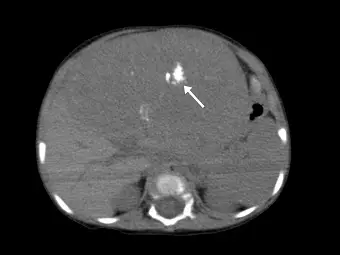

幼童患有肝母細胞瘤( hepatoblastoma ),未施打顯影劑的腹部電腦斷層顯示腫瘤內有不規則白色區塊(如下圖箭號處),經測量其密度約為 300 HU ,其最有可能為下列何種成分?

- 影像切面與技術:這是一張幼童的未施打顯影劑腹部電腦斷層(Non-contrast abdominal CT)橫斷面(Axial view)影像。

- 解剖與病灶發現:影像中可見肝臟區域有一巨大且佔位性的實質腫瘤,佔據了大部分的腹腔空間。

- 箭號指示處分析:白色箭號指著腫瘤內部一塊極高密度(hyperdense)的不規則亮白色區塊。在視覺對比上,此區塊的亮度與畫面下方的脊椎骨(vertebra)及兩側的肋骨(ribs)幾乎一致,暗示其成分與骨骼相似。

- 數值對應:題目提供該區塊的 CT 測量密度約為 300 HU。在 CT 影像學中,大於 100 HU 且視覺上呈現亮白色的物質,高度提示為鈣化或骨骼結構。